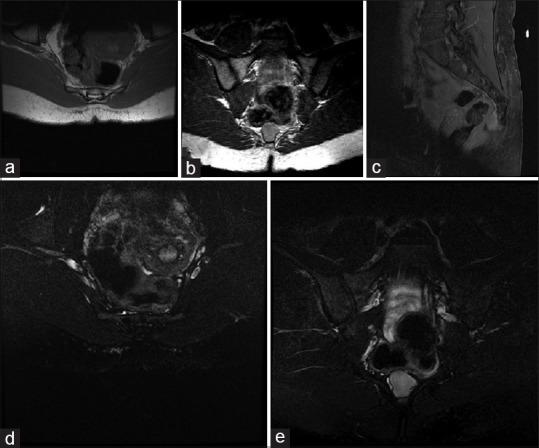

An adult female with chronic pelvic pain presented with a sacral teratoma. She failed conservative treatment and underwent a coccygectomy with an excision of the tumor. Microscopic histological analysis showed no evidence of immature or malignant elements, confirming the diagnosis of a mature, benign, cystic SCT.

一名患有慢性盆腔疼痛的成年女性被诊断为骶骨畸胎瘤。她保守治疗失败,接受了尾骨切除术及肿瘤切除术。显微镜下组织学分析未发现不成熟或恶性成分的证据,确诊为成熟、良性、囊性骶尾部畸胎瘤。